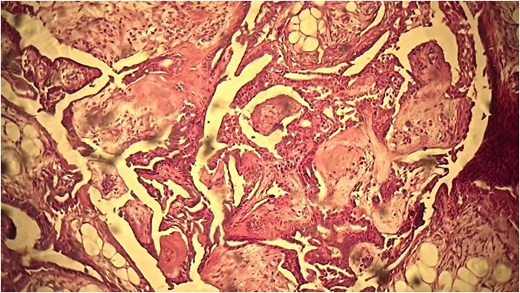

A 53-year-old Moroccan man, with no significant medical history, presented with a cheek swelling evolving over 6 months without associated symptoms. Clinical examination revealed a 1.7 cm cystic-like swelling in the cheek, suggestive of a ruptured epidermoid cyst. It was mobile and skin-colored, without inflammatory signs. Lymph nodes and salivary glands were normal. An excisional biopsy of the mass was performed. Macroscopically, it was a 1.7 cm beige, friable to firm, rounded nodule. Microscopic examination showed a well-circumscribed benign tumor proliferation composed of cysts, tubules, and ducts (Fig. 2), lined by a bilayered epithelium. The cells exhibited no nuclear atypia (Fig. 3). The fibromyxoid and chondroid stroma allowed for diagnosis without additional techniques. There was no perineural invasion or vascular emboli, and surgical margins were clear. Postoperative recovery was uneventful, and no further follow-up or additional examinations were necessary.